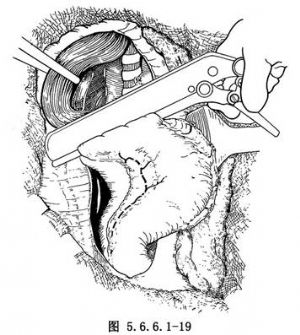

对于贲门癌,经开胸探查若肿瘤可以切除,可按常规方法将胃游离(图5.6.6.1-18)。在距肿瘤远侧3~4cm处用胃肠缝合器将胃体夹住(图5.6.6.1-19),上钉后切断。

在靠近贲门口的Kocher钳下缘0.5cm处做一浆肌层荷包缝线,暂不打结,准备经此放置吻合器主体。如果肿瘤浸润至贲门部,则距病变边缘4~6cm用胃残端缝合器进行缝合、关闭,之后在两排缝合钉之间切断胃(图5.6.6.1-36,5.6.6.1-37)。

(4)距肿瘤下缘约5cm用自动胃肠缝合器(GIA)缝合、横断胃(图5.6.6.1-44)。用一把Kocher钳夹住胃之上切缘,而将下切缘再用中号线连续缝合加固,并用细丝线间断浆肌层缝合法包埋之(图5.6.6.1-45)。